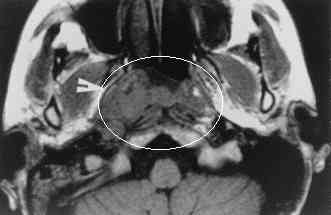

CT normal anatomyCTCTpic#1 and pic#2, CT advanced nasopharynx cancer